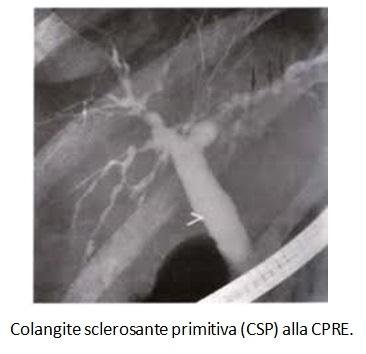

2) Colangite sclerosante E' più frequente nell'uomo tra i e i 40 a Si associa frequentemente a malattia infiammatoria intestinale Sono presenti ANCA Per fare la diagnosi bisogna escludere calcolosi biliare, precedente chirurgia sulle vie biliari, anomalie biliari congenite, cirrosi biliare, colangiocarcinoma 3) Epatite cronica autoimmune. Morelli A, Narducci F, Pelli MA, Ciccone R, Rossi L, Gubbiotti A La colangiografia retrograda per via transendoscopica nella diagnosi della colangite sclerosante primitiva Osservazione di sei casi Minerva Med 1978 Oct 31;. Colangite sclerosante primitiva By Giorgio Maria, Gaia Marniga, Federica Cadeddu, Casimiro Nigro, Pasquale Mazzeo, Serafino Vanella and Giuseppe Brisinda Topics Colangite sclerosante, Settore MED/12 GASTROENTEROLOGIA.

Morelli A, Narducci F, Pelli MA, Ciccone R, Rossi L, Gubbiotti A La colangiografia retrograda per via transendoscopica nella diagnosi della colangite sclerosante primitiva Osservazione di sei casi Minerva Med 1978 Oct 31;. Invece, le più importanti entità nosologiche primitive, che attengono alla patologia colestatica, sono la cirrosi biliare primitiva (CBP), oggi definita colangite biliare primitiva, e la colangite sclerosante primitiva (CSP) Entrambe sono sindromi colestatiche croniche, caratterizzate da una fibrosi infiammatoria dei dotti biliari, intra. Colangite sclerosante Derived from the NIH UMLS (Unified Medical Language System) Related Topics in Liver Books Cardiovascular Medicine Book Dentistry Book Dermatology Book Emergency Medicine Book Endocrinology Book Gastroenterology Book Geriatric Medicine Book Gynecology Book Hematology and Oncology Book Human Immunodeficiency Virus Book.

Colangite Sclerosante Primitiva F Rosina Presidio Sanitario Gradenigo Torino F Rosina Presidio Sanitario Gradenigo Torino Primary Sclerosing CholangitisPrimary Sclerosing Cholangitis an immunemediated inflammatory chronic cholestatic liver disease characterized by. Morelli A, Narducci F, Pelli MA, Ciccone R, Rossi L, Gubbiotti A La colangiografia retrograda per via transendoscopica nella diagnosi della colangite sclerosante primitiva Osservazione di sei casi Minerva Med 1978 Oct 31;. A Dati epidemiologici Primary Biliary Cirrhosis Incidence and Predictive Factors of Cirrhosis Development in Ursodiol Treated Patients Christophe Choperchot, Fabrice Carrat, Raoul Poupon, ReneeEugenie Poupon.

Primary sclerosing cholangitis (PSC) is an uncommon inflammatory condition, which affects the biliary tree resulting in multiple strictures, liver damage, and eventually cirrhosis The diagnosis can be made when there are classical imaging features in the correct clinical context, and secondary causes of cholangitis have been excluded 16. Si associa di frequente con malattie infiammatorie intestinali che va sempre ricercata, specie RCU, raramente Crohn.